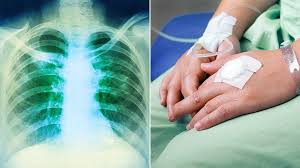

Hodgkin lymphoma is an uncommon cancer that develops in the lymphatic system, which is a network of vessels and glands spread throughout your body. Bone marrow involvement in hodgkin's disease: Протокол nccn лимфома ходжкина (лимфогранулематоз) — hodgkin_lymphoma. Hodgkin lymphoma (hl) is a type of lymphoma in which cancer originates from a specific type of white blood cells called lymphocytes. Symptoms may include fever, night sweats, and weight loss.